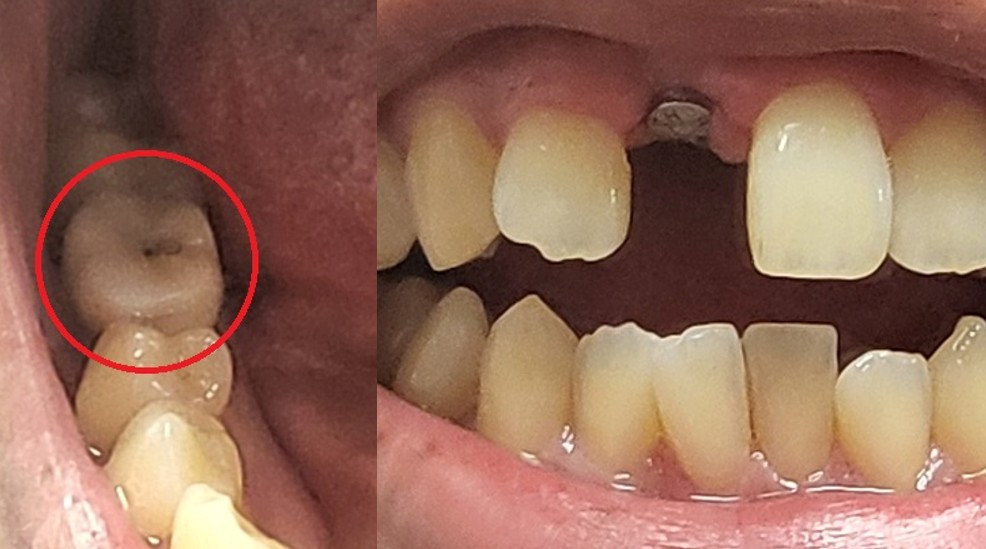

- 앞니는 임시 가짜 치아를 심지 않았다. (빠진 채로 다닙니다. 아래 사진 참조)